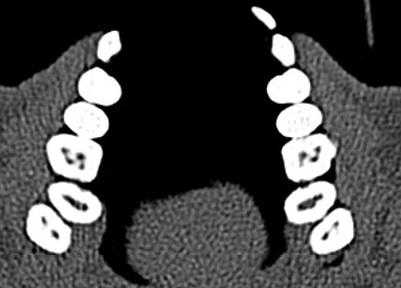

КЛКТ проводили на конусно-лучевом компьютерном томографе J. Morita Accuitomo 170, поле сканирования (FOV — field of view) — 8×8 см, угол ротации — 360, размер воксела (Voxel) — 0,16 мм.

С целью улучшения визуализации анатомических образований на компьютерном томографе при проведении сканирования применяли внутриротовой ретрактор соответствующего размера. Таким образом, отодвигая мягкие ткани губ и щек, исключали наслаивание теней и получали точную визуализацию анатомических образований пародонта.

Перед оценкой данных проводили настройку коррекции яркости и контрастности для максимальной визуализации вестибулярной костной пластинки, а также центрирование осей координат по вертикальной оси зуба для стандартизации прохождения среза.

Для повышения точности исследования проводили 3 вестибуло-оральных реформата относительно центральной оси с шагом 0,5 мм.